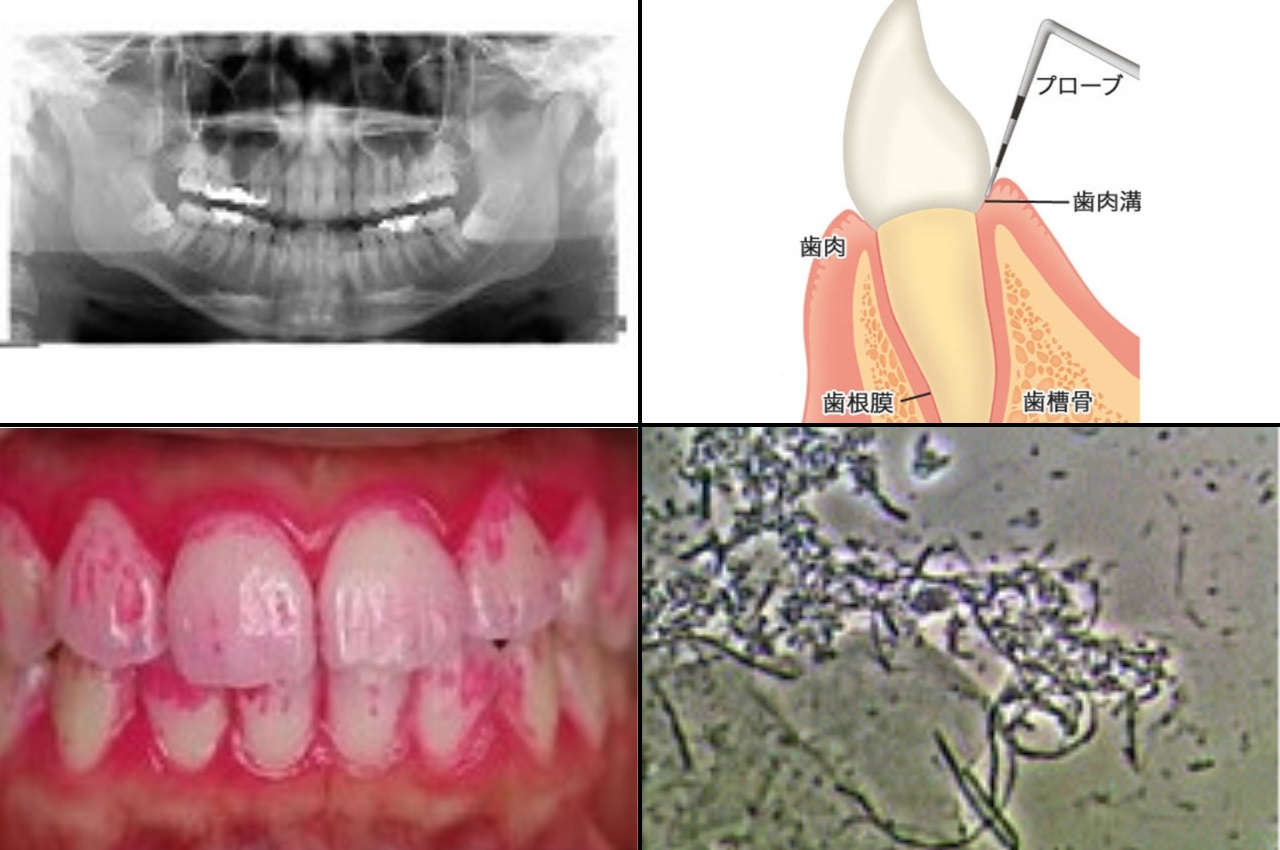

歯周病とは「細菌感染によって歯を支えているあごの骨が溶かされてしまう病気」です。

1.歯周病の精密検査

歯周病の精密検査によって得られた検査結果によって、現在の歯周病の診断を確定します。さらに、現在の進行度と感受性(遺伝的・生活習慣や全身的歯周病リスク)によって治療方針、およびおおよその治療期間を決定します。

歯周病の原因は、歯周病原細菌の感染です。そのため、歯周病の治癒に最も重要なことは、いかに歯周病原細菌が活動しにくい口腔内環境を作れるかどうかにかかっています。これには患者さん自身の毎日のブラッシングと食生活習慣の改善が不可欠です。

歯周病治療①により、ブラッシング技術を習得し、表面上の歯茎の腫れを消退させたのち、第二段階の治療として歯茎の中の歯石除去を行います。歯茎の中に歯石が付着していると、そこが歯周病原細菌の隠れ家(歯周ポケット)となってしまうため、これをきれいに除去する必要があるのですが、第一段階でブラッシング技術の習得が出来ていないと効果が半減してしまう、あるいはせっかく除去してもまたすぐに歯石が付着してしまうため、第二段階でこの処置を行います。